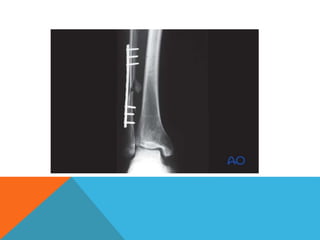

LIMITED CONTACT DYNAMIC COMPRESSION

• Modification that attempts to correct some of the design shortcomings of the DC

plate.

• Based on work by Klaue and Perren, there are three main differences in design.

– sides of the plate are inclined to form a trapezoidal cross section interrupted by

undercuts that form.

• reduces the area of contact between the plate and the periosteal surface of the

bone,

– the screw hole is made up of two inclined and one horizontal cylinder

• they meet at the same angle, permitting compression in both directions

– stress is more equally distributed

• less deformation occurs at the screw holes when contouring

• The biomechanical uses and applications of the LCDC plate are the same as those

for the DC plate.